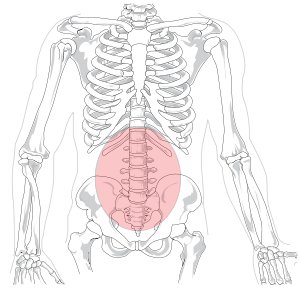

Pain in the back is a common condition, as well as lots of people experience it at some time in their lives. Usually, back pain is connected with muscle strains or soft tissue troubles. The pain might be a plain pains or an acute pain. It may be felt in the back, neck, and reduced legs. If the discomfort is severe, it may be associated with a herniated disc or another underlying clinical problem.

5. Low back pain is the fifth most common reason for all physician visits in the United States. (Source: National Institute of Neurological Disorders and Stroke)

You might not understand it, however your lower back is a complex structure comprised of vertebrae. In order to operate properly, these bones require to be stable. Nonetheless, as we age, the bones in our spinal column begin to compress. This can cause degenerative changes, which can cause a squeezed nerve. A pinched nerve can take place instantly or progressively. It may additionally occur due to an injury.

One of the most usual causes of a squeezed nerve in lower back are a stressful injury, herniated disc, or disc degeneration. It can likewise be triggered by muscle spasms or other muscular tissue issues. You might also experience symptoms of sciatica, which is a condition that is triggered by compression of the sciatic nerve. You might experience signs and symptoms like discomfort and feeling numb in the back, legs, and feet. If you experience any one of these signs and symptoms, you need to look for treatment promptly. You must additionally ensure that you obtain clinical focus if the signs and symptoms do not enhance after a couple of weeks.

A squeezed nerve in lower back may also be triggered by bad stance. If your posture is poor, you are most likely to experience this kind of pain. When you are seated for long periods of time, the back is located incorrectly, which puts additional stress on the back. You may likewise be overweight, which puts pressure on the back and also includes pressure on the nerves.